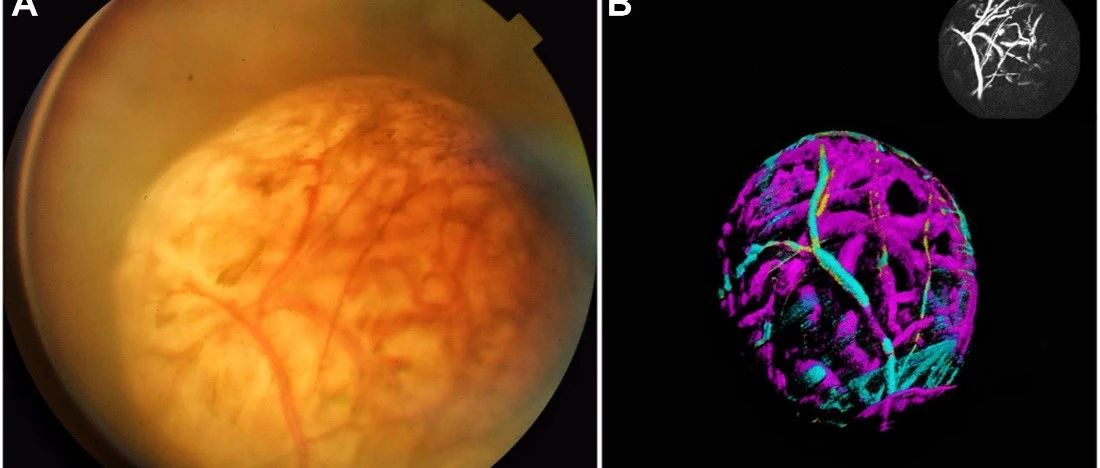

- 探索无色素脉络膜黑色素瘤双循环,《Ophthalmology》再现图湃3D血流魅力

- 近日,广州中山大学中山眼科中心的胡洁教授团队江志豪医生和蒋欣桐医生,采用图湃40万速全域扫频OCTA检查了一例罕见的无色素脉络膜黑色素瘤并发表了精彩的病例报道《Double Circulation Pattern in Amelanotic...